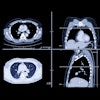

The combination of plaque quantified on coronary CT angiography (CCTA) and artificial intelligence (AI)-powered fractional flow reserve (FFR-CT) analysis can accurately predict future major adverse cardiac events, according to research published online August 8 in the American Journal of Cardiology.

Using a prototype deep-learning software application, a multinational research team led by Dr. Philipp von Knebel Doeberitz of the Medical University of South Carolina and Mannheim-Heidelberg University in Mannheim, Germany, found that FFR-CT and plaque markers derived on CCTA could identify patients who would have a future major adverse cardiac event significantly better than just CCTA stenosis grading alone.

Stenosis 50% or more and several plaque features measured on CCTA have been shown in the literature to provide prognostic power for these cardiac events, while deep learning-based FFR-CT also has been validated for identifying lesion-specific ischemia, according to the researchers. To evaluate the potential effect of a combination of the two methods, they analyzed 82 patients who had received CCTA and invasive coronary angiography for known or suspected coronary artery disease (CAD) at a single center between October 2012 and July 2017. Of the 82 patients, 18 (21%) developed a major adverse cardiac event during the study's median follow-up period of 18.5 months.

Next, the researchers retrospectively utilized prototype software from Siemens Healthineers to quantify plaque for control lesions and the lesions responsible for the cardiac event; another prototype using a deep learning-based software application from Siemens was used to perform FFR-CT analysis.